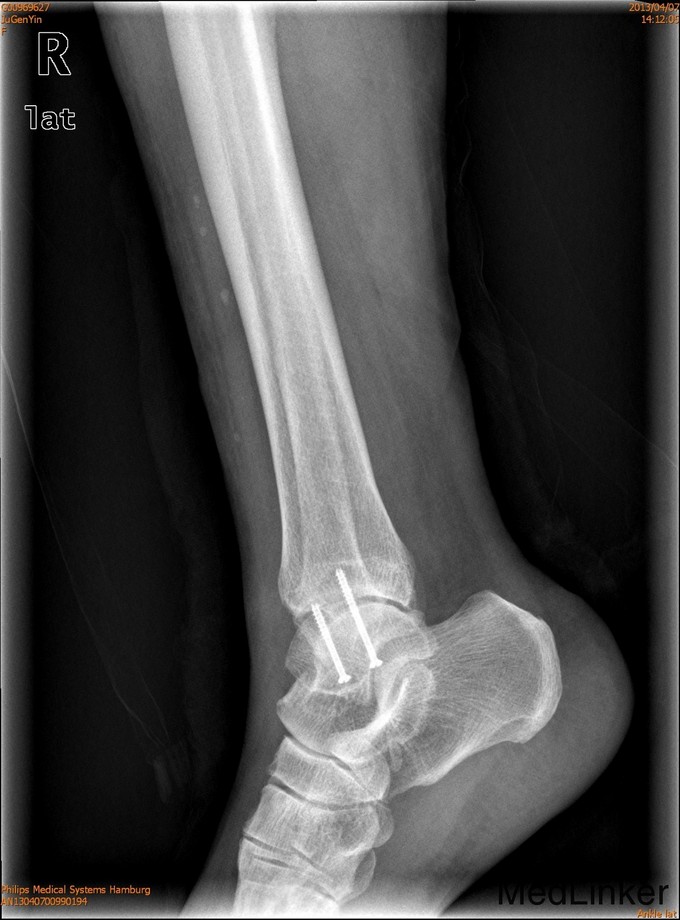

诊断为右外踝骨折,完善术前检查后于全麻下行右外踝骨折ORIF术+距腓前韧带修复术。

2年后随访患者活动可,内固定位置可,螺钉未予取出。外踝骨折可导致踝关节不稳定,手术治疗效果可。